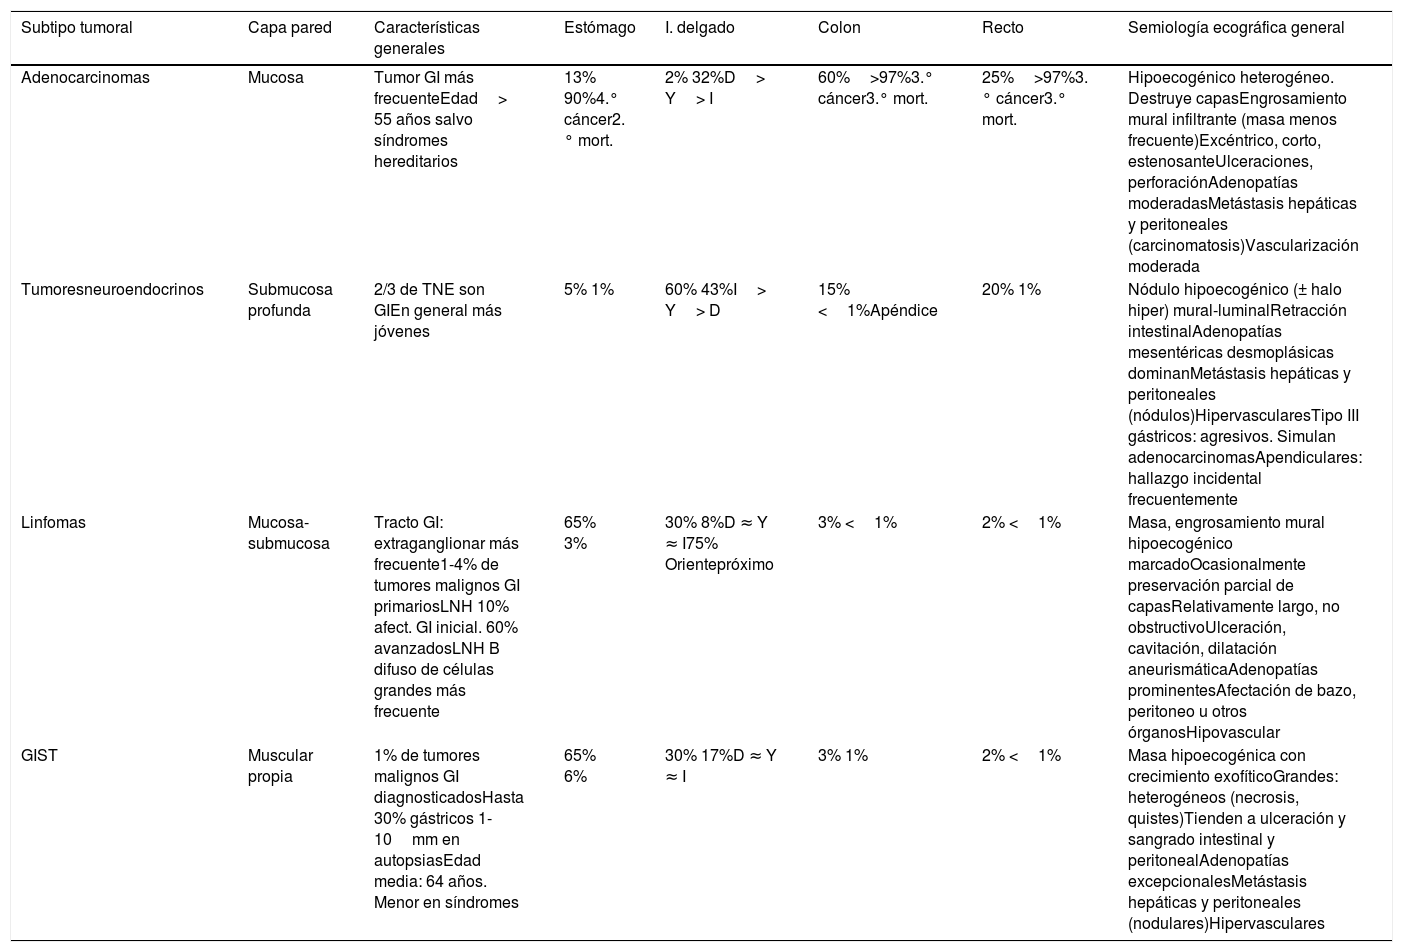

Por lo general, la neoplasia gastrointestinal se presenta como masa sólida o engrosamiento mural hipoecogénico marcado (>12 mm), corto (<10cm), asimétrico y con disrupción de la estructura en capas29. Algunos linfomas o tumores incipientes pueden preservar esta estructura, que por otro lado puede verse también interrumpida en afectación isquémica o inflamatoria transmural. El patrón ecográfico, la topografía y el contexto clínico permiten estrechar el diagnóstico diferencial y ocasionalmente aportan información exclusiva. La tabla 3 resume las características más relevantes.

Resumen de las características de los cuatro tipos principales de neoplasias gastrointestinales primarias malignas

| Subtipo tumoral | Capa pared | Características generales | Estómago | I. delgado | Colon | Recto | Semiología ecográfica general |

|---|---|---|---|---|---|---|---|

| Adenocarcinomas | Mucosa | Tumor GI más frecuenteEdad> 55 años salvo síndromes hereditarios | 13% 90%4.° cáncer2.° mort. | 2% 32%D> Y> I | 60%>97%3.° cáncer3.° mort. | 25%>97%3.° cáncer3.° mort. | Hipoecogénico heterogéneo. Destruye capasEngrosamiento mural infiltrante (masa menos frecuente)Excéntrico, corto, estenosanteUlceraciones, perforaciónAdenopatías moderadasMetástasis hepáticas y peritoneales (carcinomatosis)Vascularización moderada |

| Tumoresneuroendocrinos | Submucosa profunda | 2/3 de TNE son GIEn general más jóvenes | 5% 1% | 60% 43%I> Y> D | 15% <1%Apéndice | 20% 1% | Nódulo hipoecogénico (± halo hiper) mural-luminalRetracción intestinalAdenopatías mesentéricas desmoplásicas dominanMetástasis hepáticas y peritoneales (nódulos)HipervascularesTipo III gástricos: agresivos. Simulan adenocarcinomasApendiculares: hallazgo incidental frecuentemente |

| Linfomas | Mucosa-submucosa | Tracto GI: extraganglionar más frecuente1-4% de tumores malignos GI primariosLNH 10% afect. GI inicial. 60% avanzadosLNH B difuso de células grandes más frecuente | 65% 3% | 30% 8%D ≈ Y ≈ I75% Orientepróximo | 3% <1% | 2% <1% | Masa, engrosamiento mural hipoecogénico marcadoOcasionalmente preservación parcial de capasRelativamente largo, no obstructivoUlceración, cavitación, dilatación aneurismáticaAdenopatías prominentesAfectación de bazo, peritoneo u otros órganosHipovascular |

| GIST | Muscular propia | 1% de tumores malignos GI diagnosticadosHasta 30% gástricos 1-10mm en autopsiasEdad media: 64 años. Menor en síndromes | 65% 6% | 30% 17%D ≈ Y ≈ I | 3% 1% | 2% <1% | Masa hipoecogénica con crecimiento exofíticoGrandes: heterogéneos (necrosis, quistes)Tienden a ulceración y sangrado intestinal y peritonealAdenopatías excepcionalesMetástasis hepáticas y peritoneales (nodulares)Hipervasculares |

D: duodeno; I: íleon; GI: gastrointestinal; GIST: tumor del estroma gastrointestinal; LNH: linfoma no Hodgkin; TNE: tumor neuroendocrino; Y: yeyuno.

En las casillas de afectación topográfica, el porcentaje a la izquierda hace referencia a la proporción de tumores de ese subtipo de tumor maligno primario (de entre todos los gastrointestinales) que asienta en esa localización en concreto. El porcentaje a la derecha indica qué proporción de todos los tumores malignos primarios en esa localización representan los de ese subtipo en concreto. Por ejemplo, el 60% de los TNE gastrointestinales asientan en el intestino delgado, donde representan el 43% de todos los tumores malignos primarios. Son cifras aproximadas, promediadas y redondeadas por los autores a partir de diversas fuentes.